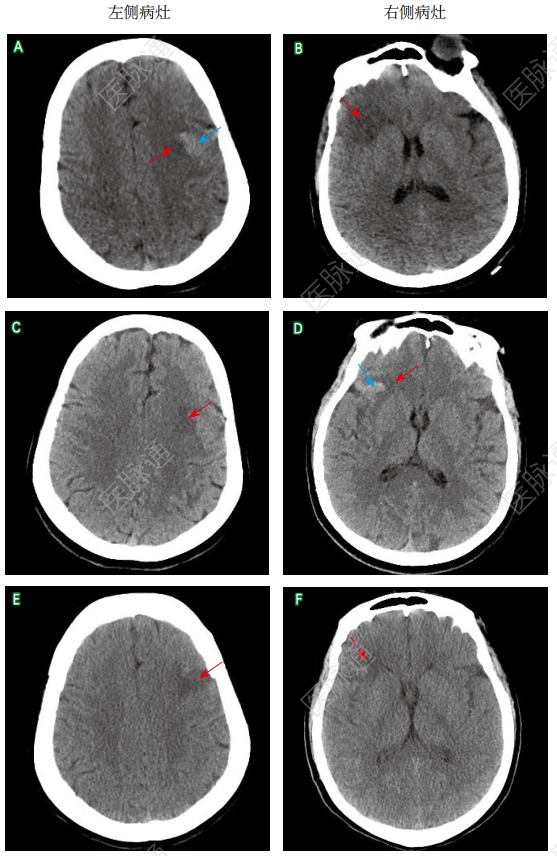

【头颅CT检查】发病后第4天急诊头颅CT检查显示左侧额叶梗死并发出血、右侧额叶梗死(图2A~B);发病后第12天复查头颅CT示左侧额叶出血吸收,右侧额叶梗死灶内新发出血(图2C~D);发病后第21天再次复查头颅CT示右侧额叶出血吸收,双侧额叶残留低密度影(图2E~F)。头颈部CTA检查未见异常(图3)。